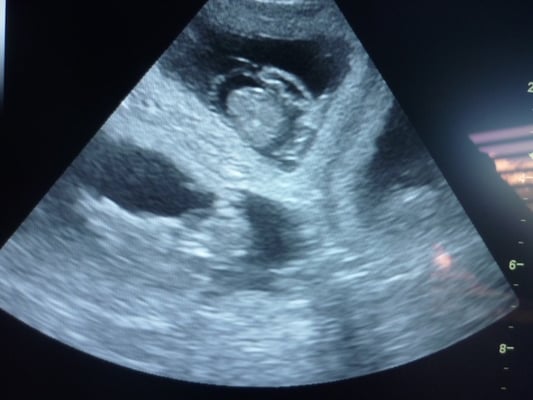

7.2.2018 aujourd’hui nous avons la confirmation que Fidji aura des bébés vers mi-mars !

Le 5 janvier 2018, Fidji et Hector se sont rencontrés… en espérant qu’ils auront de beaux bébés au début du mois de mars…

Fidji et Hector